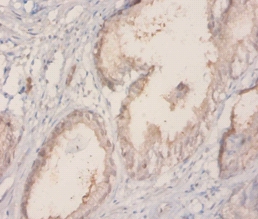

Immunohistochemical analysis of paraffin-embedded humankiney using #42572 at dilution of 1:20.

Immunohistochemical analysis of paraffin-embedded humanprostate using #42572 at dilution of 1:20.